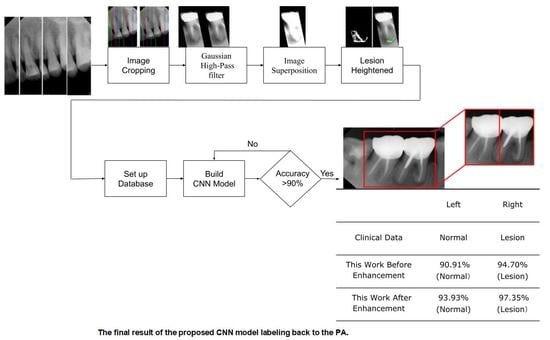

- In the image cropping preprocessing part, this study adds the adaptive threshold and angle rotation technology. Compared with the existing methods, this method significantly improves the image clarity and accuracy of a single tooth image.

- This study proposes an advanced image enhancement technique for apical lesions. It adds raw grayscale images and Gaussian high-pass filtered images to highlight the possible lesion areas and changes the color of the possible lesion area to green. Experiments show that the accuracy of the model is improved by more than 10% which proves that the proposed method is intuitive and effective.

- The innovation of this work is to realize the classification of various diseases. It can simultaneously judge a variety of different types of dental diseases (such as apical lesions, fillings, etc.), and the obtained final accuracy of the model proposed in this paper is as high as 93%. AlexNet even improves the accuracy up to 96.21% which is 4% higher than the state-of-the-art in [23].

3. Results

| Tooth Position in Figure 13 | Left | Right |

|---|---|---|

| Clinical Data | Normal | Lesion |

| This Work Before Enhancement | 90.91% Normal | 94.70% Lesion |

| This Work After Enhancement | 93.93% Normal | 97.35% Lesion |